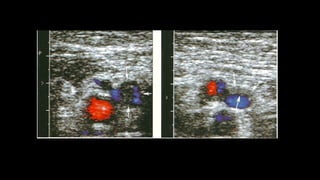

Figura 10 Vena perforante mayor de 3 mm con reflujo en el

Valsalva).

Doppler de miembrosinferiores en la insuficiencia venosa 5 VSM VFC Figura 8 Corte longitudinal a nivel del ostium, donde se debe hacer la medición del diámetro de la VSM. - Se debe mencionar y evaluar la existencia de venas vari- cosas que no tengan relación con las safenas, así como también hay que establecer cuál es su procedencia (por ejemplo: vena pélvica), ya que la ligadura de las safenas puede no ser necesaria16 . En síntesis, el objetivo del examen es determinar el punto de fuga, la presencia de venas epifasciales insuficientes y el punto de reentrada, indicando la existencia de perforantes insuficientes y su localización. Parámetros a evaluar en el paciente safenectomizado con tratamiento de termo obliteración 1) Buscar si se evidencian tramos de safena e informar dónde comienzan y terminan. 2) Es importante tener en cuenta que en la etapa posquirúr- gica inmediata se pueden ver imágenes hiperecogénicas en la luz de la vena, habitualmente secundarias al tra- tamiento de termo obliteración con láser. Esto no debe ser confundido con trombosis y tiene que ser informado como safena termo-obliterada. ARTICLE+Model RARD-60; No. of Pages 8 6 Vena perforante Vena perforante insuficiente HD P T R 12,03,0 P T R 12,03,0 Figura 10 Vena perforante mayor de 3 mm con reflujo en el

reverso ante lasmaniobras de Valsalva en la unión safena- femoral (viraje de color rojo, en descanso a color azul, en Valsalva). +0,86 m/s –0,864 s m/s –0,11 +0,11 Vena femoral VSM Figura 5 Imagen que demuestra el cierre valvular correcto sin reflujo en la VSM con el Doppler color y espectral. Figura 7 Insuficiencia de la VSM en el tercio medio del m ante las maniobras de Valsalva. - Para examinar el eje de la VSP, con el paciente de e das al operador, se realizan cortes transversales en la posterior de la pantorrilla (de caudal a cefálico), vis zando la vena safena parva y calculando el reflujo e distintos niveles. Debe consignarse si es o no tortuo a qué altura desemboca en la vena poplítea (si es lo hace)15 , midiendo la distancia desde la planta del A su vez, hay que evaluar la presencia o no de la safena parva del muslo y, en caso de que esté prese definir si esta es suficiente o insuficiente. - A nivel del hueco poplíteo se busca la existencia de re en la vena poplítea. - Si se descubre insuficiencia de la VSP, también debe indicar si el ostium está involucrado o si el reflujo se i más caudalmente, si hay presencia de venas epifasc dilatadas y los puntos de reentrada del flujo. - Es necesario explorar las venas tibiales posteriores, a riores y peroneas. ARTICLE IN PRESSRARD-60; No. of Pages 8 4 H. Berardi, A. Ciccioli VSM Izquierda + ,07 – ,07 m/s +55,90 –54,98 cm/s 2 1 0 Vena femoral VSM 5,3s Figura 3 Doppler espectral con corte transversal evidencia una VSM suficiente ante las maniobras de Valsalva. HD 20 10 0 10 20 T R 12,03,0 P VSM HD Figura 6 Corte transversal de la VSM que muestra un aumento de las velocidades anterógradas (por encima de la línea de base), ante las maniobras de Valsalva.